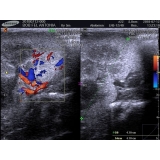

Cada vez mais cães e gatos tem feito parte da vida das nossas vidas e muitas vezes são vistos como mais que animais de estimação e sim como membros das famílias. Esse membro da sua família merece o melhor em exames laboratoriais para animais. A Amazing Pets oferece os mais tecnológicos e modernos exames laboratoriais para garantir a saúde de seu animal. Com muita rapidez, fornece os resultados dos exames que dirão qual o melhor tratamento para as doenças de seus bichos de estimação. Com exames de hematologia, tomografias, raio-x, entre outros, a Amazing fornece um diagnóstico rápido para curar as patologias que acometem seu animal.